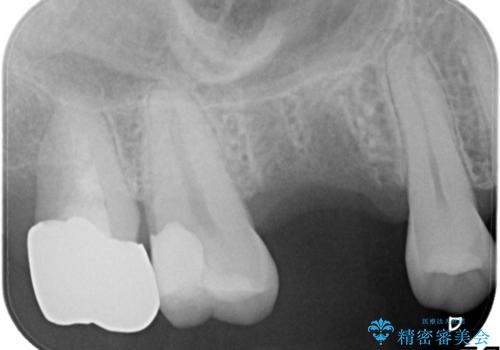

- 歯がないところを何とかしたいとのことで来院されました。

右上奥歯を抜歯された状態でした。

インプラントとブリッジ治療の2通りの治療方法のご提案をさせていただき、インプラント治療をすることとなりました。

インプラントを埋入する際に骨の高さが不足していたので、骨造成も同時に行う計画としました。